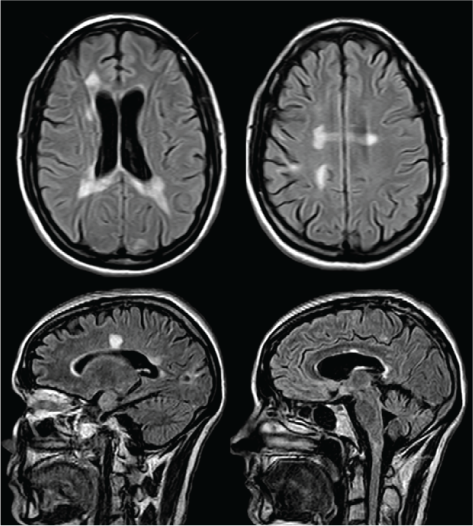

Two months after the completion of PLEX, the patient was ambulating with assistance, and her EDSS score was 6.5. She was started on disease-modifying therapy with natalizumab given the aggressive nature of her disease and approval through her private drug benefits. However, during the next year she demonstrated slow progressive neurologic decline consistent with a secondary progressive MS diagnosis; her MRIs did not show any new lesions or recurrence of her tumefactive lesions (Figure 2). Thus, 1 year later, natalizumab was stopped owing to clinical progression and an EDSS score of 7.5 to 8.0.

Axial and sagittal fluid-attenuated inversion recovery images at the same levels as in Figure 1, 2 years later, showing resolution of the medullary lesion, coalescence of the periventricular lesions, and interval development of diffuse brain atrophy